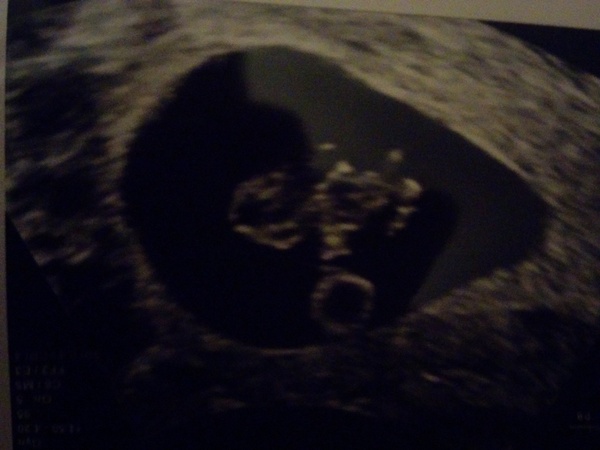

I am due on 1 August. I had my 8+1 scan today and thankfully everything was fine, Smile big relief as I have had few symptoms. I hope everyone has good news too xx

Oh my god am I seeing that right? It already looks like a baby!

Wow carna that's a really good pic!

carnassials · 22/12/2015 19:03

Thanks! He/she is only 1.68 cm long so the scan is greatly zoomed in. We even saw some movement! I can't believe it after two years trying and IVF. Good luck all xx Smile

Congratulations carnnasials Xmas Smile

carna that is a fantastic scan pic, so pleased to hear all is well and what a special time to have seen your little wriggly baby after waiting so long - wonderful Christmas present!!